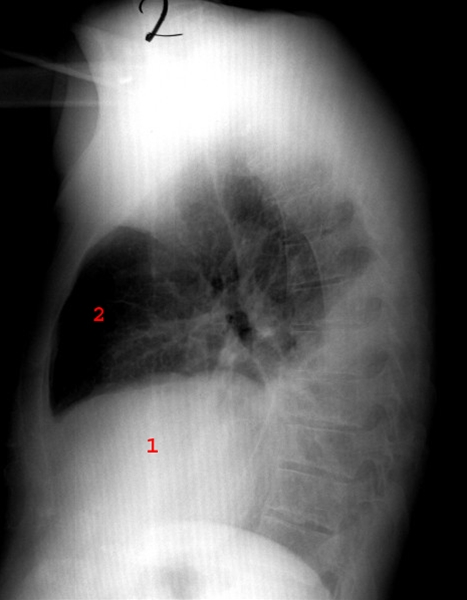

Pleuropneumoni, røntgen, sideoptagelse

Røntgenbilledet viser pneumonisk infiltrat bagtil og nedadtil i thorax med pleuraeffusion.

1: hjertet

2: luft fortil i brystkassen